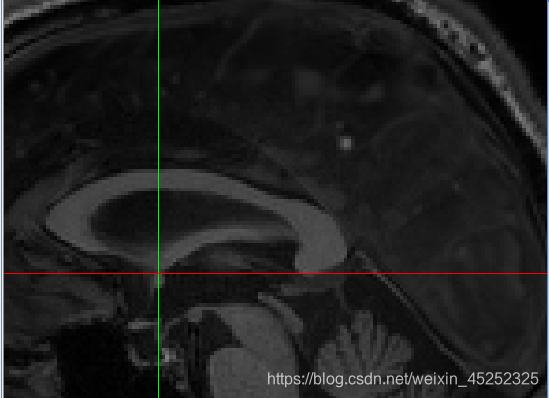

(4)第二个目标是标记PC inferior edge

•这更难,因为PC在1毫米分辨率下显示不好

•幸运的是,PC始终位于脑导水管的顶部,这确实显示得很好(至少,如果脑脊液被MRI脉冲序列适当抑制的话)

因此,如果你看不到PC,就在脑导水管顶部找到中矢状位,标记为PC下缘(inferior edge)

脑导水管,细长部分(网图:比较明显):

一般PC和AC的Y轴坐标相同,即第一个坐标